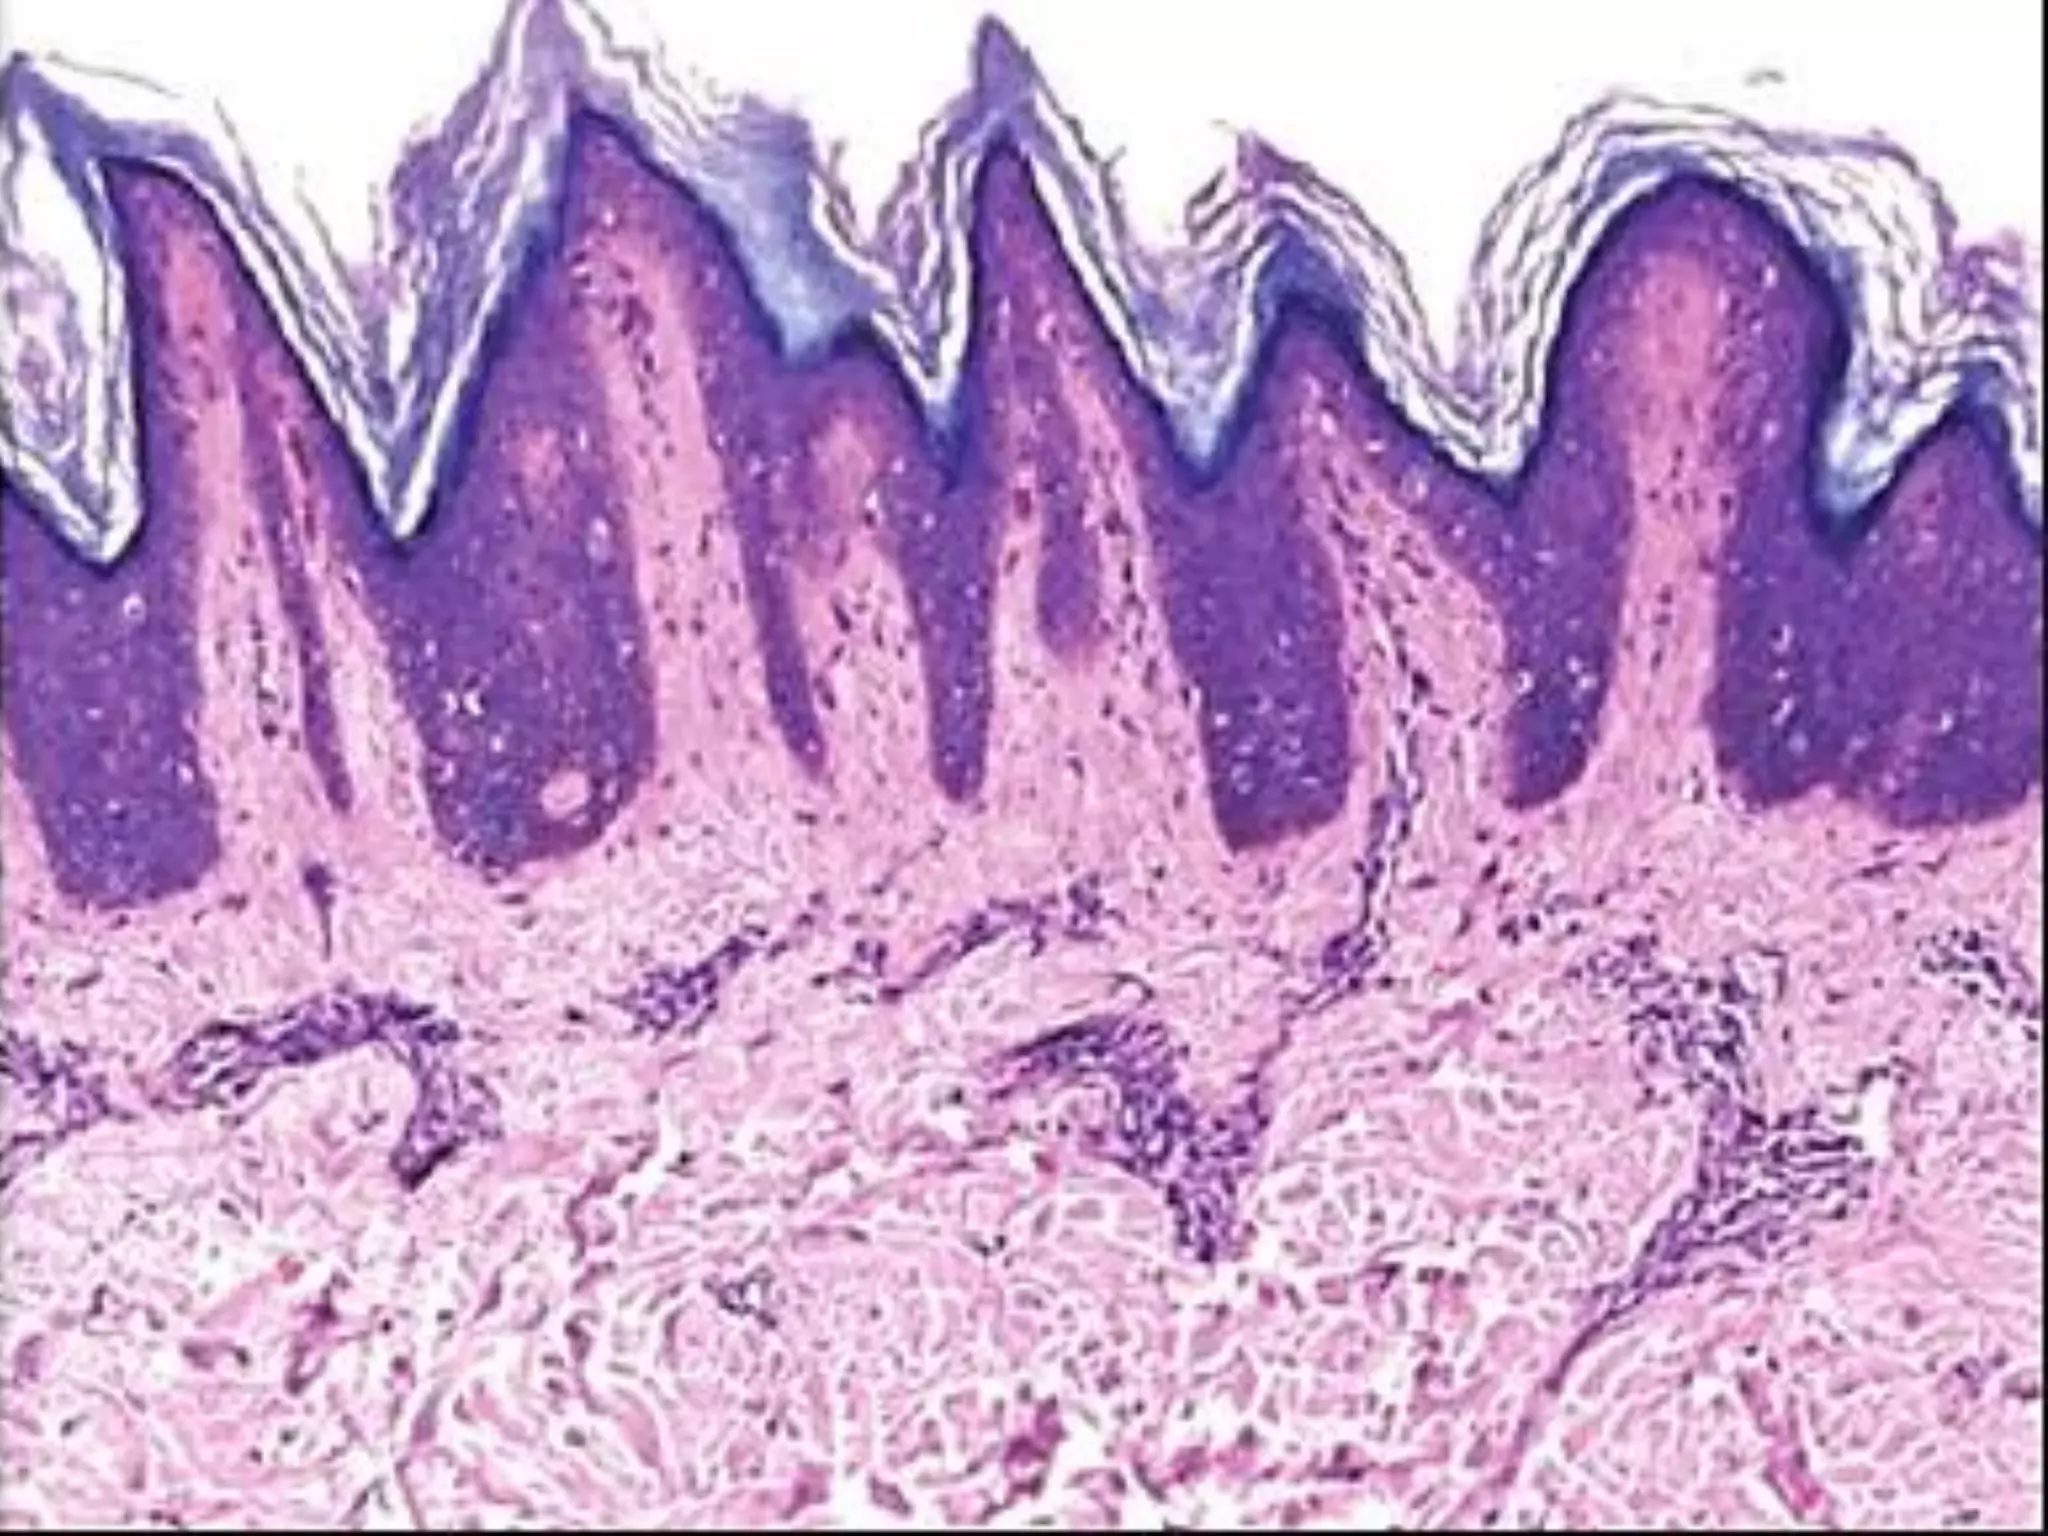

The document provides an overview of dermatopathology, including methods and techniques for skin biopsies such as shave, punch, and ellipse methods. It discusses key terms associated with dermatopathology, such as acantholysis and granulation tissue. Additionally, it references presentations by professionals in the field and essential dermatology resources.